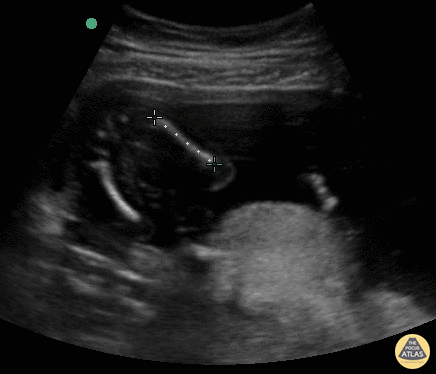

OB Dating Atlas - Week 17 - Femur Length

A 34-year-old G6P5 with an LMP of “a few months ago” presents for vaginal spotting. She had a positive UPT 5 days ago. FL measures 2.42cm, consistent with a 17w2d IUP. General Rules: Measure diaphyseal length only (excluding epiphysis) with the length of the bone perpendicular to the ultrasound beam A simple measure to get in a critically ill medical or surgical patient to determine if the fetus is viable outside of the uterus [4] Accuracy3: ± 7 - 17 d